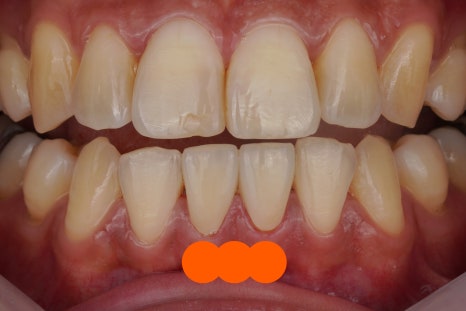

입안에 충치가 있을 때 우리가 가장 걱정하는 건 "신경치료해야 하나요?" 겠죠. 뽑아야하는 것 까진 아닌것 같고 '신경치료'라는 매우 길고 힘든 과정이 걱정이 되실 겁니다. 그럴 때 웬만하면 그렇게 하지 않고 치아를 살려가는 방향으로 가장 보수적인 진단을 하는 치과 그런 치과가 있다면 조금은 안심이 되지않을...

하지만 진단 단계에서 부터

미리 몇단계 앞서 나가는게

어느새 당연시되어진 이 분위기를

바꿀 필요가 있다고도 생각합니다.

치과 광고를 보면 너도나도

임플란트만 내세우는 상황..😢

치아에 남은 여명을 굳이 앞당겨

임플란트로 대체시키기보다는

그 수명을 최대한 오래 끌고가는

보존적인 치료법으로

선택권을 넓혀드리고 싶습니다.